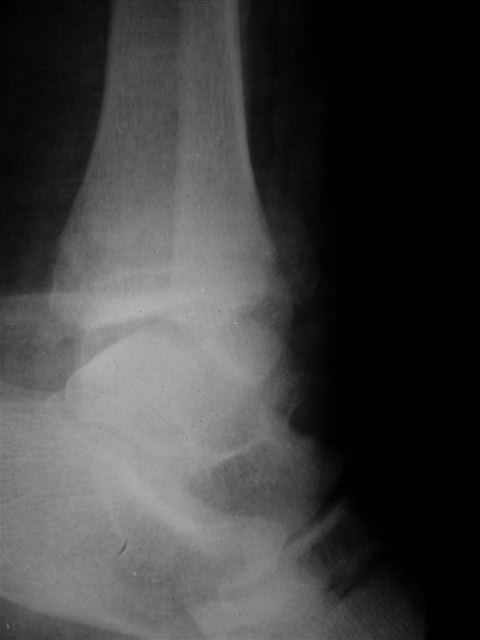

> интересуюсь тактикой лечения повреждений голеностопного сустава.

Ничего сверхъестественного, но если есть интерес, то в понедельник пересниму Рг-граммы и отправлю.

Уважаемый Иван,

Я предупреждал, что ничего сверхъестественного. Каюсь, что одна из спиц прошла несколько дальше, чем нужно было, но главное - перелом стабилизирован и больной работает суставом в полном объёме, несмотря на представленную раннее травму коленного сустава.